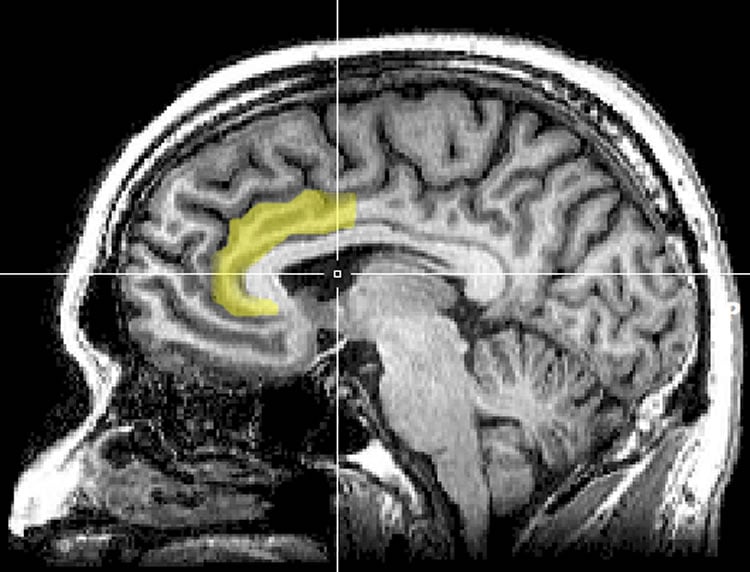

MRI images taken at the end of the treatment phase revealed that in depressed subjects the drug significantly increased the volume of one region of the brain, the anterior cingulate cortex, while decreasing the volume of this same region and the hippocampus in non-depressed subjects. Both of these areas are highly interconnected with other areas of the brain; are critical in a wide array of functions including memory, learning, spatial navigation, will, motivation and emotion; and are implicated in major depressive disorder.

In humans, Shively said, volume differences in neural structures have been noted in depressed and non-depressed individuals, with the most commonly reported differences being smaller volumes of the cingulate cortex and hippocampus in depressed people. One potential mechanism through which drugs such as Zoloft can be effective as antidepressants is by promoting neuron growth and connectivity in these brain regions.